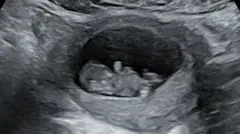

Mas, após um sangramento no início da gravidez, um teste mostrou que Rhiannon havia sofrido um aborto espontâneo com oito semanas.

Mas então veio o ultrassom de 20 semanas, que revelou que o bebê – que o casal chamou de Hudson – tinha uma forma grave de síndrome do coração esquerdo hipoplásico, uma doença cardíaca congênita rara em que o lado esquerdo do coração é subdesenvolvido.